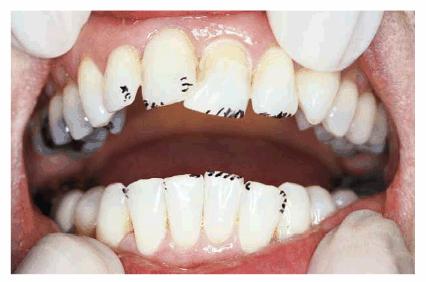

PROBLEM: A 56-year-old businessman presented with a desire to straighten

his anterior teeth. In addition, he was concerned about the wear and

irregularity of the incisal edges of his teeth (see Figures 24-4A 24-4B, and 24-4C). Orthodontics was presented as a

first option, but the patient declined this treatment option because of the

Figure 24-4A: Pretreatment-anterior view. Note the prominence of tooth #7 due to significant rotation and the slightly shortened appearance of tooth #10.

Figure 24-4B: Pretreatment-incisal view. Variations in available arch space for the lateral incisors are evident.

Figure 24-4C: Pretreatment-view of normal smile. Irregular incisal edges and incisal embrasures create an unbalanced esthetic appearance.